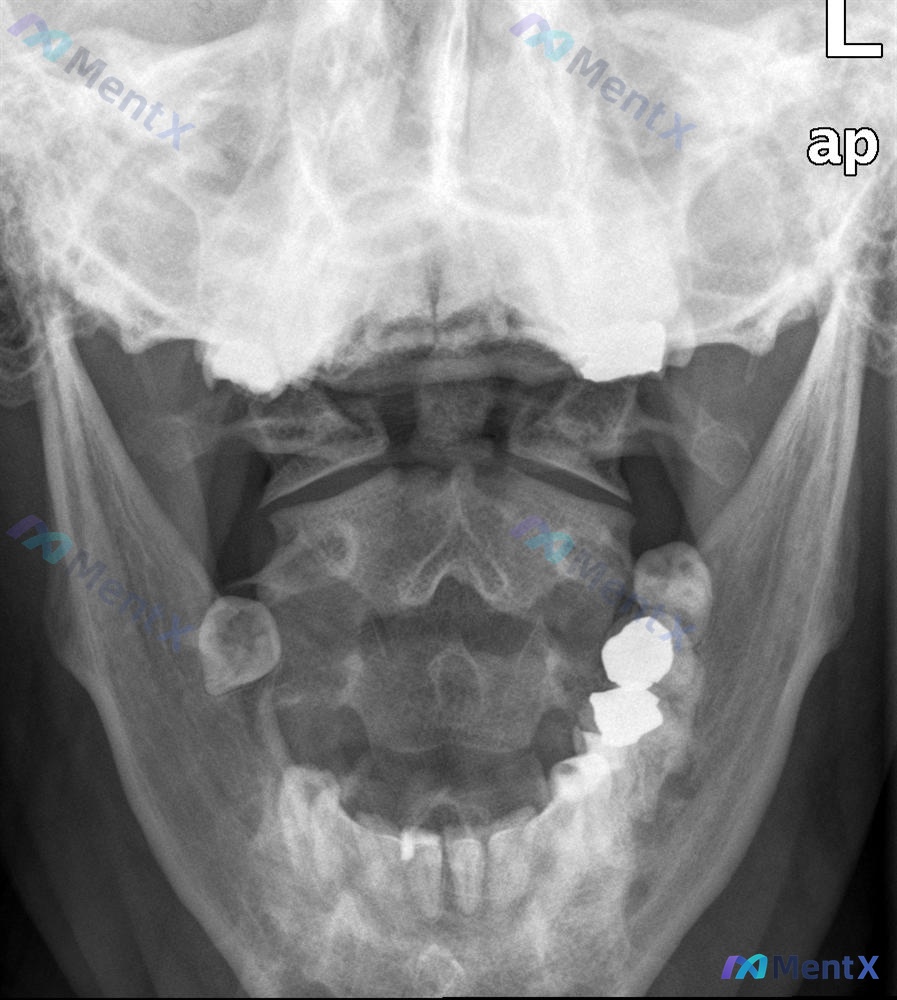

整理到一个上颈椎损伤的病例讨论材料,先看基础信息: - 患者:45岁男性 - 就诊原因:运动交通事故就诊急诊科 - 主诉:颈部疼痛 - 查体:ASIA E(神经功能完好) - 影像:张口颈椎X光片、矢状位CT、CT轴位血管造影 影像分析提示: 1. 枢椎(C2)齿状突基底部骨折,骨折块与椎体分离 2...